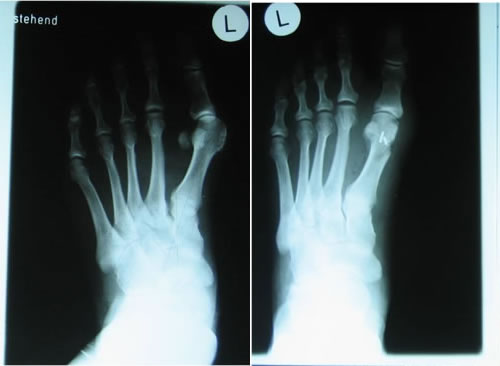

Die

Darstellungen der einzelnen knöchernen Abschnitte des

Bewegungsapparates können bei chronischen Beschwerden

(Verschleißerkrankungen) und bei Unfällen (z.B.

Sportverletzungen mit Verdacht auf Knochenbruch) mit moderner

und strahlenarmer Röntgentechnik sofort in der Praxis

erfolgen und ausgewertet werden.